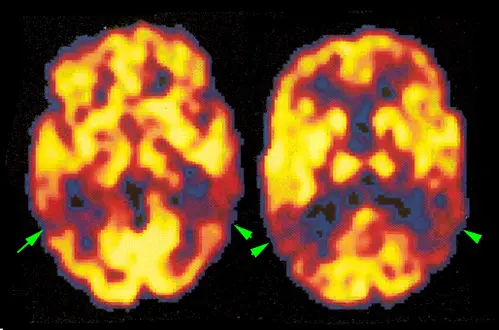

Los estudios funcionales, utilizando la tomografía de emisión de positrones y glucosa marcada con F18 permiten estudiar el metabolismo de diferentes áreas del cerebro. En la enfermedad de Alzheimer suelen observarse áreas de hipometabolismo en las zonas posteriores de los lóbulos temporal y parietal

Pulsar y arrastrar la imagen para ver las áreas de hipometabolismo